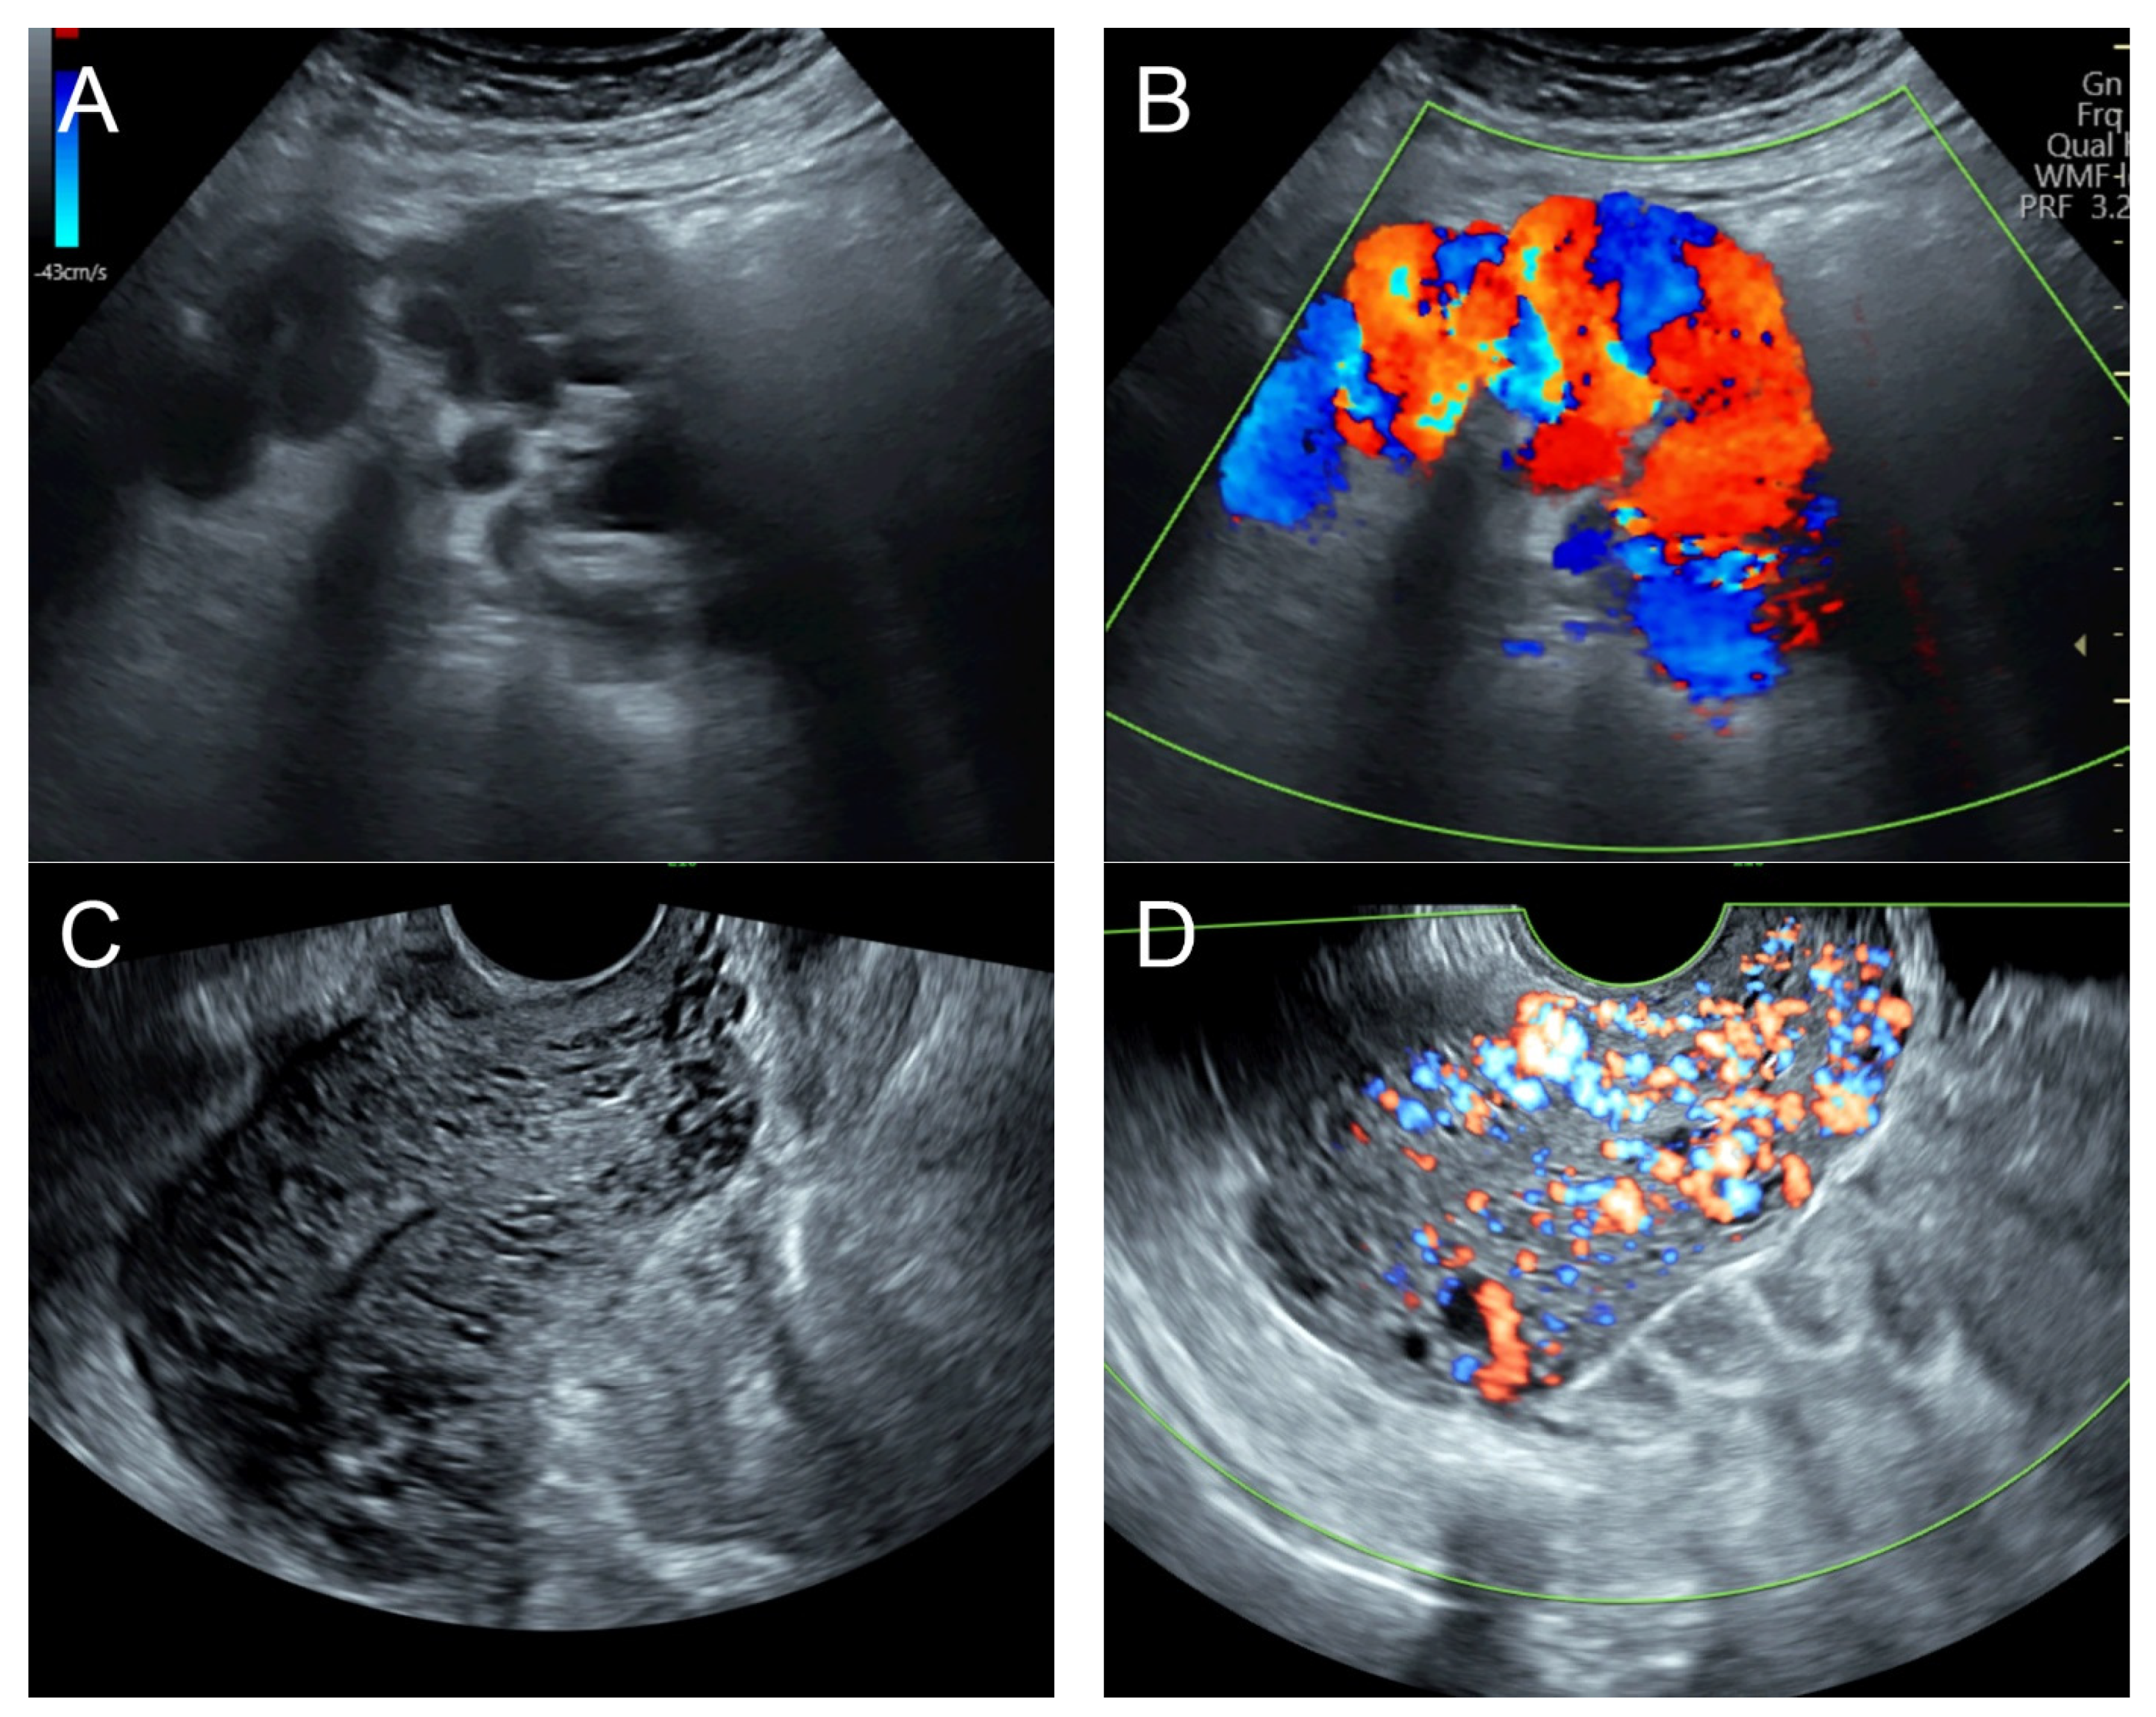

(A) Transabdominal grayscale ultrasound: transverse scans of suprapubic area showed suboptimal-quality image of the uterus, which displayed ill-defined soft tissue mass, non-visualized endometrial lining, hypoechoic areas of the uterus. No normal architecture of the uterus could be demonstrated. (B) Color flow mapping (the same area of figure (A)) showed markedly vascularized uterus, involving throughout the uterus intense vascularity with a chaotic, multidirectional flow. (C) Transvaginal color Doppler ultrasound showed markedly vascularized uterus, involving throughout the uterus intense vascularity with a chaotic, multidirectional flow. (D) Abdominal CTA revealed innumerable tortuous dilated vessels in the pelvic cavity, along the entire uterine wall. The lesions were fed by multiple arterial feeders, which were displayed as tortuous dilated arteries of the bilateral uterine arteries, right ovarian artery, and right inferior epigastric artery. Multiple draining veins demonstrated early venous opacification, namely the bilateral internal iliac veins and right ovarian vein. The CTA findings confirmed uterine AVM.